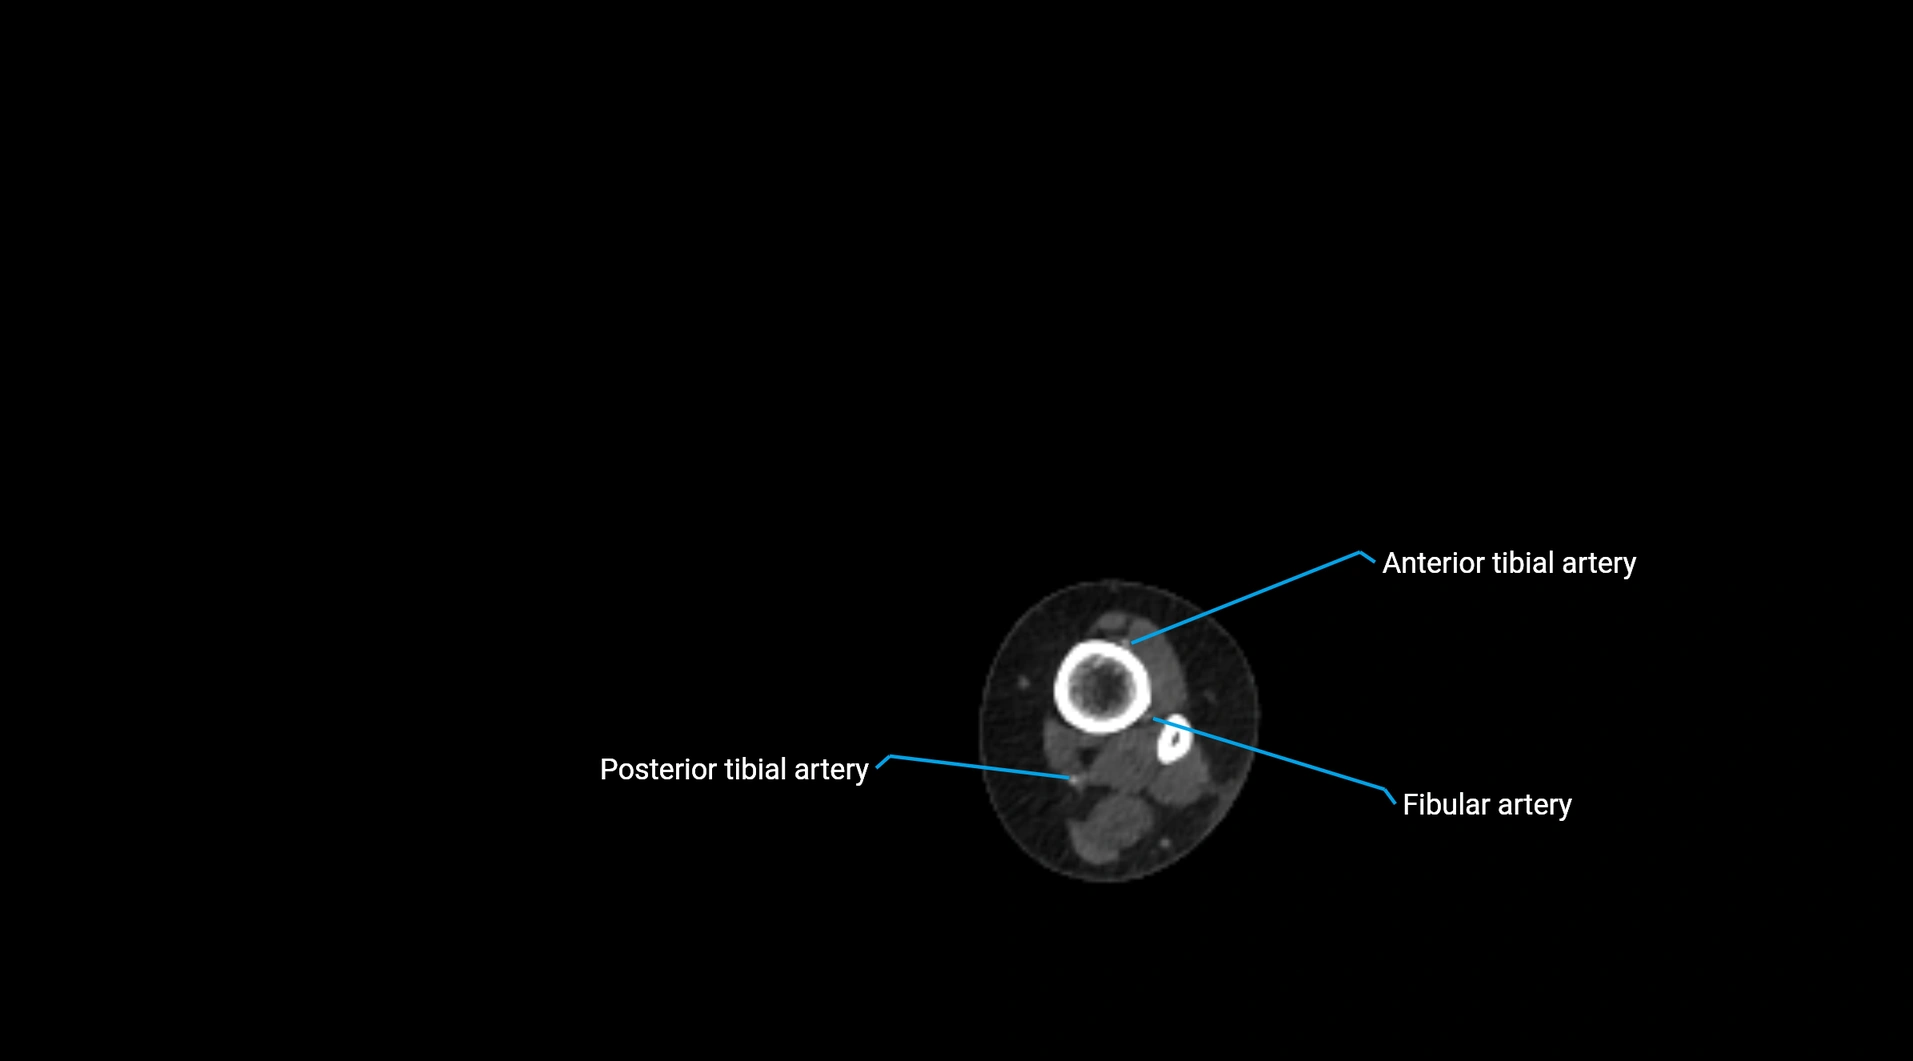

CT Appearance

Non-contrast CT:

• Appears as a tubular soft tissue structure anterior to vertebral bodies

• Calcified atherosclerotic plaques appear as hyperdense foci along the wall

• Useful for screening abdominal aortic aneurysm (AAA) size and mural calcification

Contrast-enhanced CT (CTA):

• Gold standard for abdominal aortic imaging

• Provides excellent detail of lumen, wall, aneurysm, thrombus, and branch vessels

• Multiplanar and 3D reconstructions help in aneurysm measurement, stent graft planning, and dissection evaluation

• Detects acute rupture, traumatic injury, or occlusion with high sensitivity